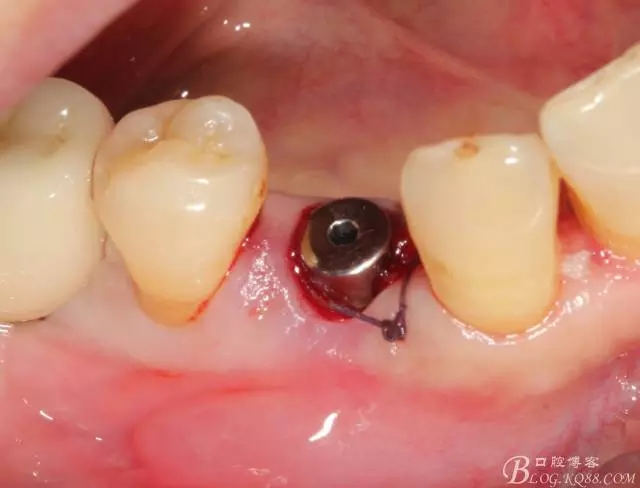

種植體頰側(cè)還是沒有完全被骨壁包繞,但是不要緊,不需要植骨

穩(wěn)定性還可以,就直接上了愈合基臺

頰側(cè)空隙塞了膠原塞 簡單縫合,全程0翻瓣,很高調(diào)的告訴患者,術(shù)后不太會有反應(yīng)的。

44號牙位術(shù)前照片

拔牙 當(dāng)然這種手術(shù)我必須不翻瓣零翻瓣

簡單備洞以后植入種植體 植體和頰側(cè)空間距離大于2毫米 注意沒有植骨

這個角度更能看到植體與頰側(cè)骨壁的空間了